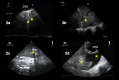

Background: The COVID-19 pandemic has placed an extraordinary strain on healthcare systems across North America. Defining the optimal approach for managing a critically ill COVID-19 patient is rapidly changing. Goal-directed transesophageal echocardiography (TEE) is frequently used by physicians caring for intubated critically ill patients as a reliable imaging modality that is well suited to answer questions at bedside.

Results: Although transthoracic echocardiography can provide the information needed in most patients, there are specific scenarios in which TEE represents the modality of choice. TEE provides acute care clinicians with a goal-directed framework to guide clinical care and represents an ideal modality to evaluate hemodynamic instability during prone ventilation, perform serial evaluations of the lungs, support cardiac arrest resuscitation, and guide veno-venous ECMO cannulation. To aid other clinicians in performing TEE during the COVID-19 pandemic, we describe a set of principles and practical aspects for performing examinations with a focus on the logistics, personnel, and equipment required before, during, and after an examination.

Conclusions: In the right clinical scenario, TEE is a tool that can provide the information needed to deliver the best and safest possible care for the critically ill patients.